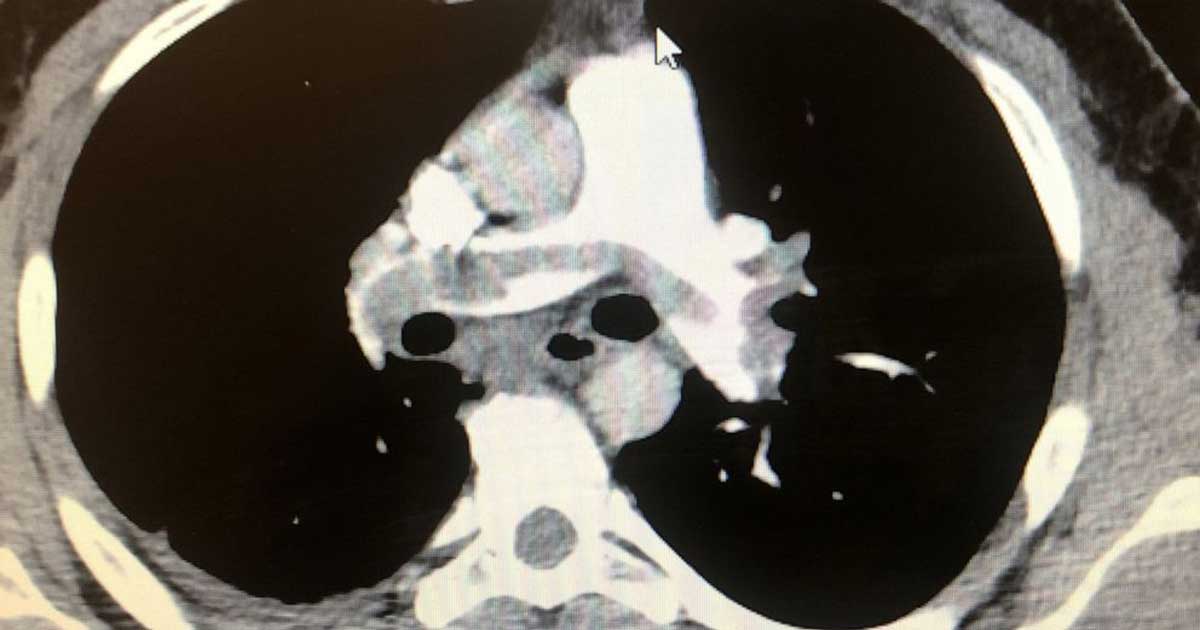

A hospital in New Orleans admitted a man in his 30s after developing shortness of breath, chest pain and an abnormally rapid heart rate – and later on tested positive for COVID-19.

Doctors realized that these symptoms are also typical for someone with pulmonary embolism – a deadly blood clot that can move from the leg up and may damage the heart.

While the patient had no known underlying medical conditions, travel history or surgeries, his blood work had shown signs of heart damage.

The patient’s cardiovascular consult, Dr. Siyab Panhwar, is thankful that they “were able to find this and treat this early, otherwise it probably would have killed him.”